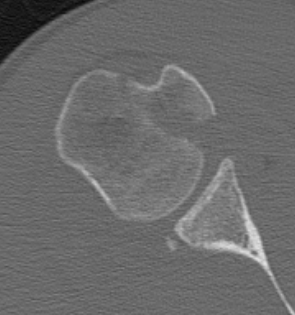

Four part

Avascular necrosis (AVN)

In most fractures, arcuate artery is disrupted, but head survives

- posterior circumflex artery is sufficient

- risk increases with amount of displacement

- 4 part fracture 30%

- 3 part fracture 15%